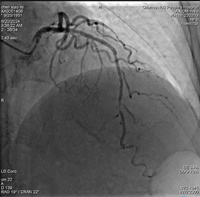

8个月前因心绞痛入院冠脉造影检查,提示前降支中段、远段均有严重狭窄,当时远段病变普通球囊及切割球囊均不能扩张,只予中段病变处植入一枚支架。本次患者胸闷、胸痛考虑犯罪血管为前降支远段病变,IVUS检查可见>270°钙化环,本次直接给患者使用国内最新的冲击波球囊,采用血管内冲击波治疗。选择一枚2.5mm*12mm冲击波球囊分别送至前降支远段钙化部位,总共发放3组冲击波,冲击波结束后,造影可见钙化部位狭窄明显减轻,经IVUS检查可见钙化环多处断裂,随后由远至中段原支架远端串联植入2枚支架。整个手术过程中,患者无任何不适症状。